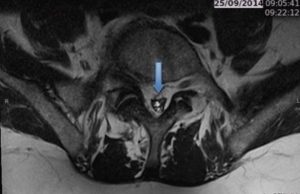

Hérnia de Disco L5 / S1 no canal vertebral no lado esquerdo

Esta patologia representa cerca de 80% das causas de dor lombar em pacientes jovens (20-50 anos), em particular entre trabalhadores com elevada carga física.